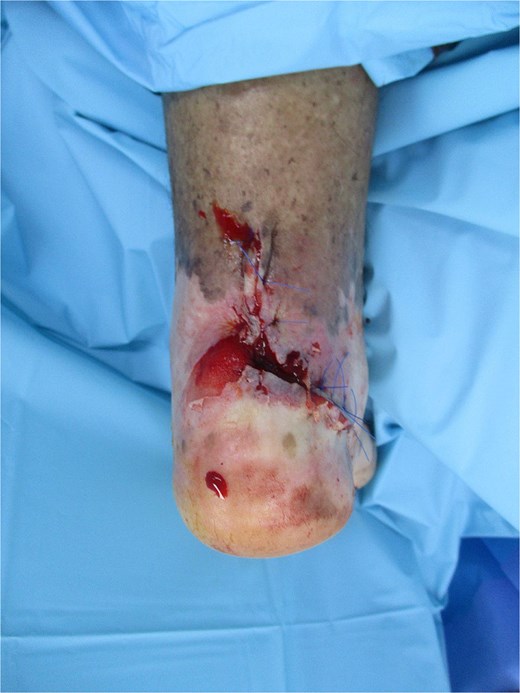

Peripheral arterial disease and diabetic neuropathy can mask early malignant change and delay presentation, as likely occurred in this case [5, 6, 10]. Similar malignant transformations have also been reported in chronic burn scars [10]. Interventions with the goal of improving perfusion of the vasculature, oncological evaluation for staging of malignancy, and surgical management with complete excision and reconstruction are required to achieve the best outcomes. Close medicosurgical collaboration achieved global management and, ultimately, curative limb treatment with limb salvage surgery [12]. In chronic ulcers such as SCC, complete excision with clear margins is crucial, as inadequate resection increases recurrence and metastasis risk [12]. In the present case, early identification, vascular optimization, and regional advancement flap reconstruction led to wound healing and functional limb preservation (Fig. 3). Reports of SCC in atypical anatomical sites underscore the importance of vigilance in unusual locations [12].

Completely healed retrocalcaneal region at 4 months post-surgery and adjuvant radiotherapy following regional advancement flap reconstruction, demonstrating durable coverage and limb preservation.

At 4 months of follow-up, the wound remained healed with no local recurrence or distant metastasis, and the patient was ambulatory with protective footwear.